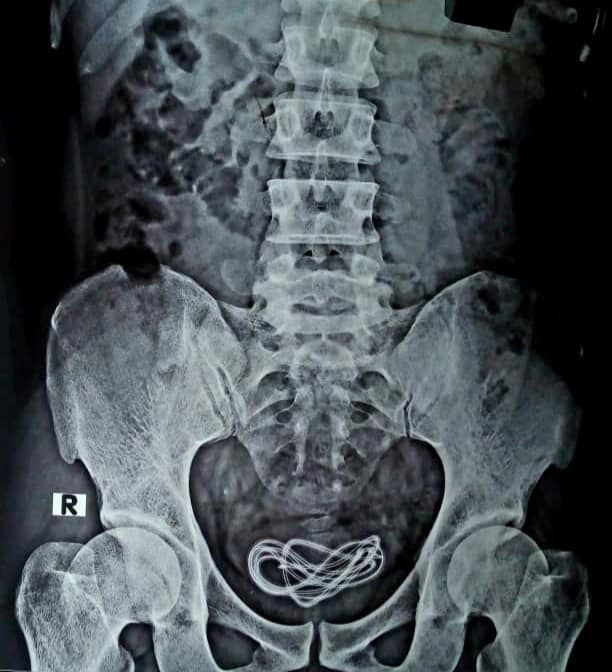

ดร.วัลลีอูล อิสลาม ศัลยแพทย์เจ้าของเคส เปิดเผยว่า ทางทีมแพทย์ได้ตรวจอุจจาระของคนไข้รายดังกล่าว พร้อมทั้งดำเนินการส่องกล้อง แต่ก็ไม่พบตำแหน่งของสายชาร์จ จากนั้นเมื่อทำการผ่าตัด ก็ไม่พบว่ามีสิ่งผิดปกติในระบบทางเดินอาหารของเขา ทางทีมแพทย์จึงทำการเอกซเรย์ ในระหว่างที่คนไข้อยู่บนเตียงผ่าตัด จนพบความจริงว่า สายชาร์จโทรศัพท์เจ้าปัญหา อยู่ในกระเพาะปัสสาวะ

แพทย์รีบดำเนินการช่วยเหลือผ่าตัด นำสายชาร์จโทรศัพท์ออกมาจากระเพาะปัสสาวะของคนไข้ โดยพบว่าสายชาร์ดังกล่าวมีความยาวเกือบ 2 ฟุต หรือประมาณ 60 เซนติเมตร การผ่าตัดสำเร็จไปได้ด้วยดี ขณะนี้คนไข้อาการเริ่มฟื้นตัวแล้ว